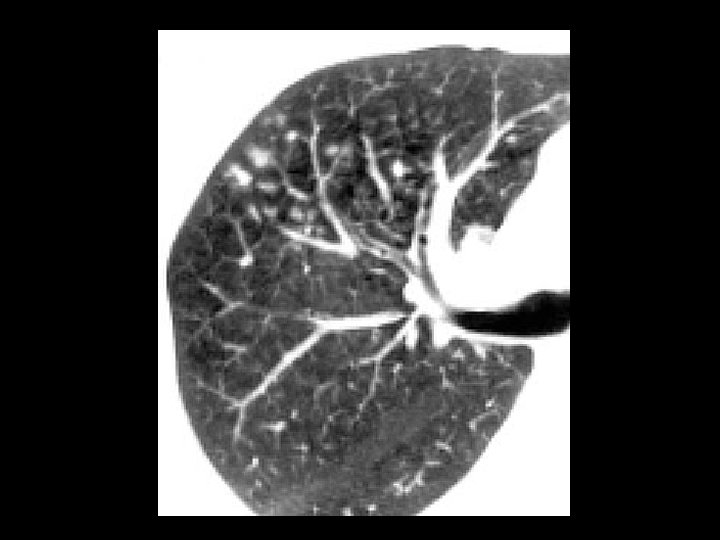

Sarcoidosis • Findings: – diffuse centrilobular nodules – nodular thickening of the interlobular septa – lymphadenopathy = “Garland’s triad” • ddx: – lymphangitic carcinoma